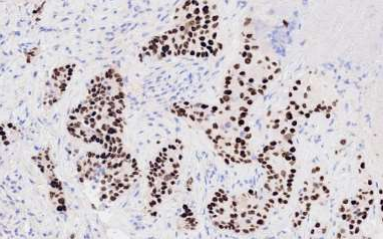

Fig.2: Iliac bone, IHC of pan-CK reflecting an epithelial origin.

As described in figure 1, the right iliac bone showed metastatic carcinoma positive for panCK, HMWCK, CK7, CK8/18, CEA and HEPAR1 (focal).  Possible primary sites included pancreaticobiliary, upper gastrointestinal tract and lung. See the details of figure 1.